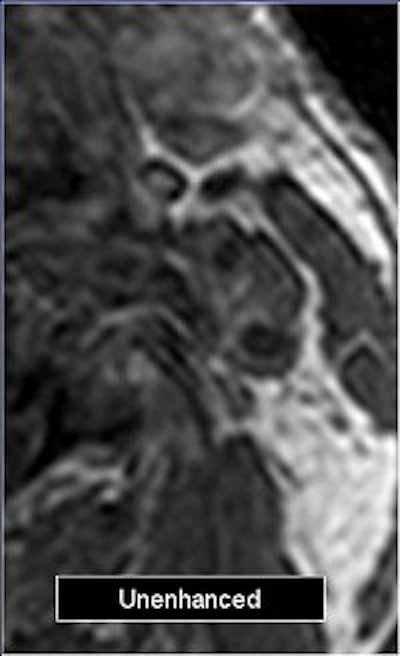

![]() |

| Angiographic image of a patient with 55% stenosis of the common carotid artery. |

Electronic subtraction (unenhanced minus enhanced axial images) was performed. Internal carotid stenoses were graded on maximum intensity projection (MIP) and multiplanar reformatted (MPR) coronal images. North American Symptomatic Carotid Endarterectomy Trial (NASCET) criteria were applied to judge the percentage of stenosis.

Plaque enhancement was evaluated on axial images by two radiologists in consensus on a four-point scale (0 equaled no enhancement; 3 equaled clear enhancement). They looked at enhanced, unenhanced, and electronic subtraction images.